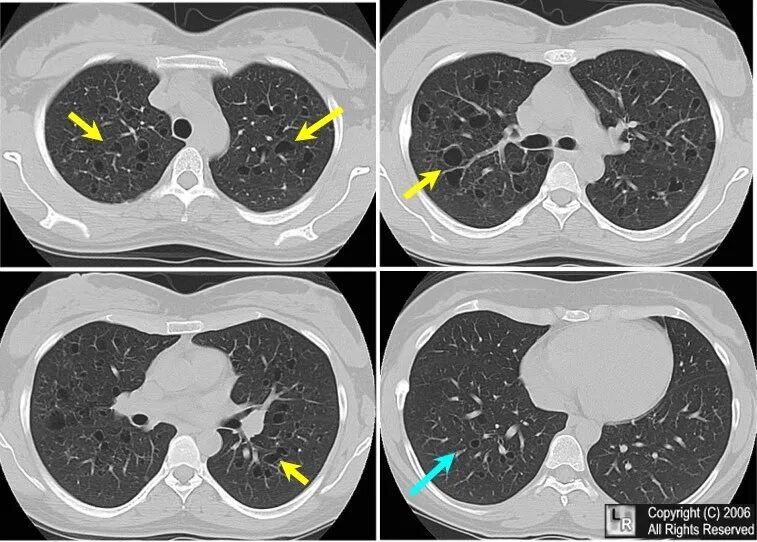

Гистиоцитоз легких